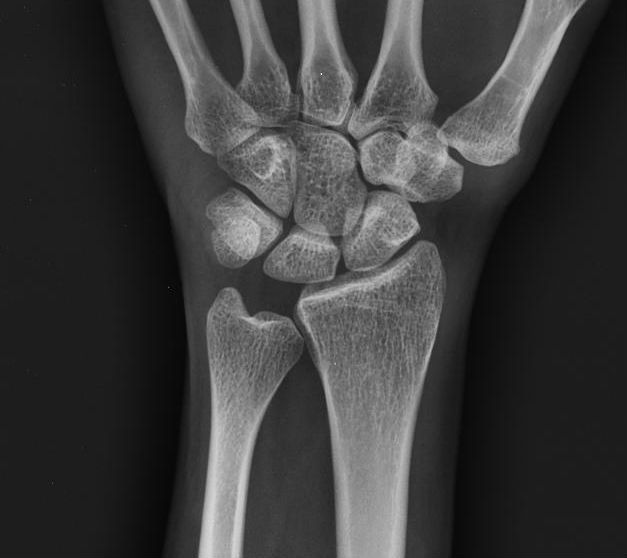

What conditions are associated with the pathological finding of this XR? What would you expect to find on physical exam?

Ulnar Positive Variance

What conditions are associated with the pathological finding of this XR?

Ulnar Negative Variance

Pathophysiology of altered ulnar variance

Ulnocarpal Abutment